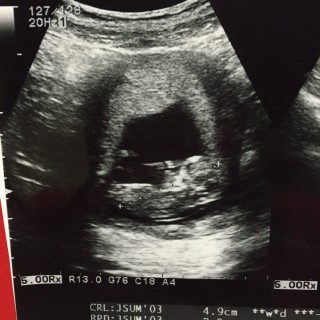

4,9㎝。順調です!右が頭です☆